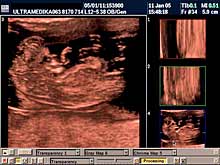

C) III trimestar trudnoće

od 24. do 40. nedelje trudnoće

Indikacija za ultrazvučni pregled:

- Procena funkcije bubrega, organa abdomena, srca i cirkulacije likvora

u mozgu.

Napomena: Na svakom pregledu do kraja trudnoće.

- Stalna procena ehostrukture organa ploda i njegov ukupni porast.

Napomena: Kod "hiperehogenih bubrega" procena renalnih aretrija CPD.

Stalna procena volumena pluća, želudca i veličine creva.

- Procena bolesti histiogeneze mozga ploda od 26 nedelje gestacije.

Napomena: Procena moždane cirkulacije Broadband - CD i CPA i/ili 3DCPA.

- Procena izostanka treće faze embriogeneze mozga

OD 26 NEDELJE DO KRAJA

TRUDNOĆE.

- Registrovanje destruktivnih lezija mozga fetusa.

Napomena: Mogu

nastati krvarenja mozga zbog nedostatka vitamina K (hemoragija

intrakranijalis - HIC), hipoksično-ishemične promene koje dovode do

periventrikularne i subkortikalne leukomalacije - PVL i SCL.